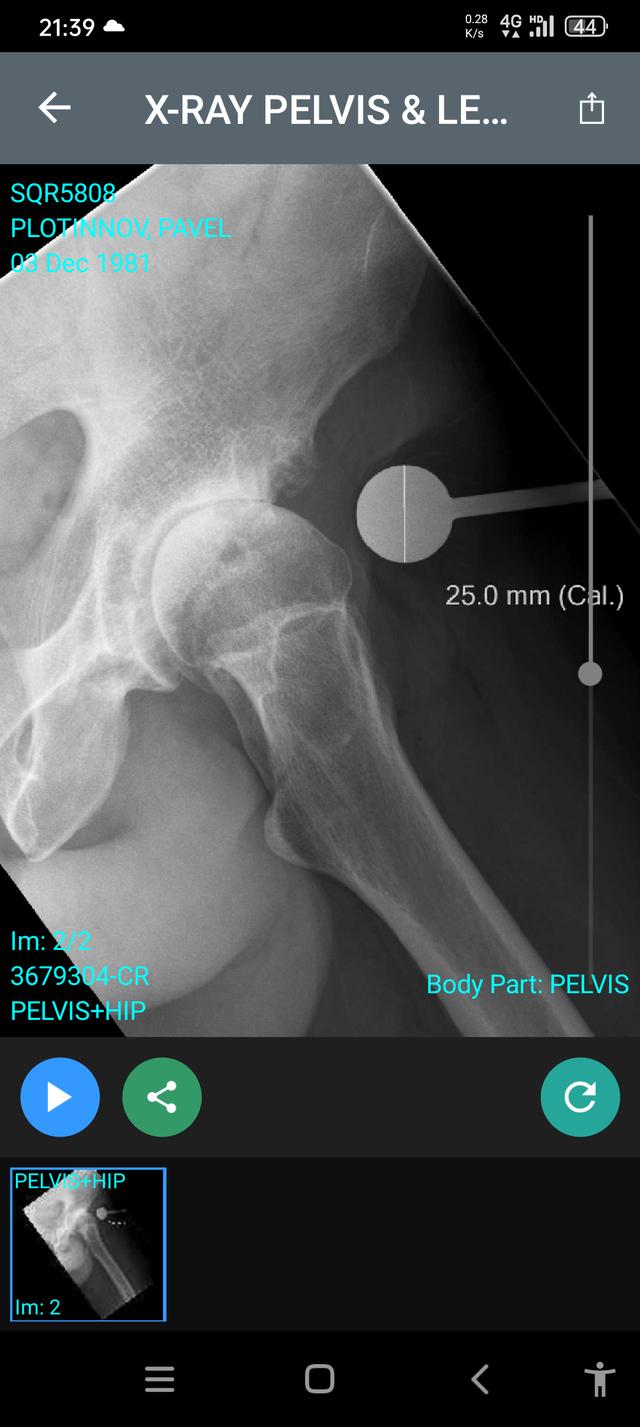

• Letter from Hamilton Radiology

Main image

Advanced left arthropathy with extensive subchondral cystic change and subarticular sclerosis.

Less advanced moderate right hip arthropathy.

Previous L5/S1 anterior lumbar interbody fusion.

Holy F... that's some brutal terminology